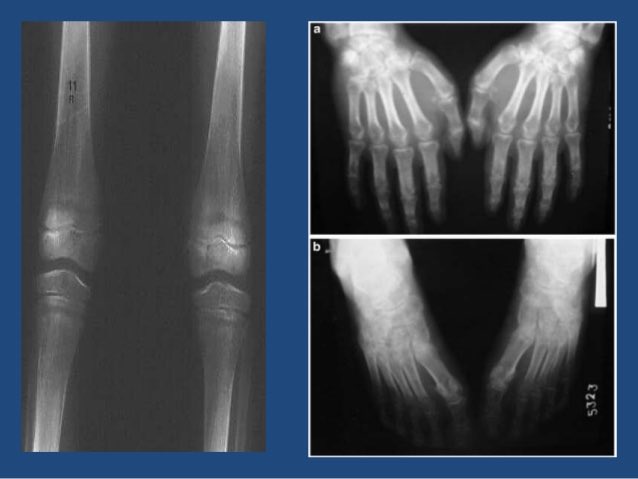

?Osteoporosis?(هشاشة العظام)

نقص كثافة العظام

?Diagnosis

كيف نشخص هشاشة العظام؟

?non Laboratory (X-ray ,CT-scan )☢️أشعة العظام